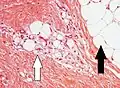

Histopathology of liposarcoma, H&E stain, with the main features:[5]

- Spindle cells with enlarged, hyperchromatic nuclei.

- Apparently univacuolated adipocytes (may look normal).

- Lipoblasts (multivacuolated), but neither necessary nor sufficient for diagnosis of liposarcoma. -

Lipoblasts are seen in liposarcoma[7] and characteristically have abundant multivacuolated clear cytoplasm and a dark staining (hyperchromatic), indented nucleus.